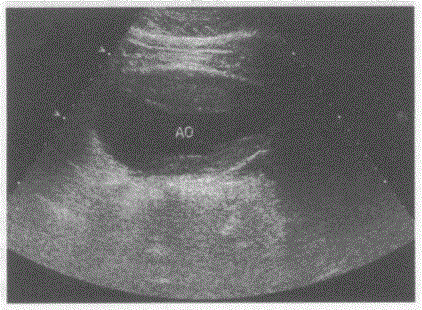

问题 临床资料:男,66岁,自述腹部不适1年余。确诊高血压20年,口服降压药,血压控制差。 超声综合描述:腹主动脉肠系膜上动脉水平一髂动脉分叉水平呈梭形,内径5.1cm,前后壁均可见中等回声,显示长度前壁10.1cm,后壁7.8cm,后方无声影,该段残余管腔内径2.5cm,CDFI:中等回声内充盈缺损。见下图及彩图。 {图1} 超声提示:

选项 A.腹主动脉假性动脉瘤 B.腹主动脉瘤并附壁血栓形成 C.腹主动脉夹层动脉瘤 D.大动脉炎

答案 B